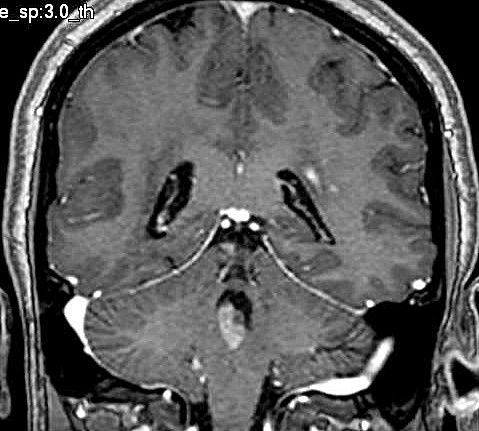

| Fem. 17a. |

| Nódulo sólido homogêneo preenchendo o III ventrículo, com limites precisos, com hipossinal em T1 e hipersinal em T2 e FLAIR, que se impregna por contraste paramagnético. Lesão menor implantada no assoalho do IV ventrículo provavelmente representa disseminação por via liquórica. |

| CORTES AXIAIS, T1 COM CONTRASTE | ||

| F. 17a. Tumor teratóide rabdóide atípico de III ventrículo. RM | HE | VIM, GFAP | HHF35, desmina, 1A4 | AE1AE3, EMA |